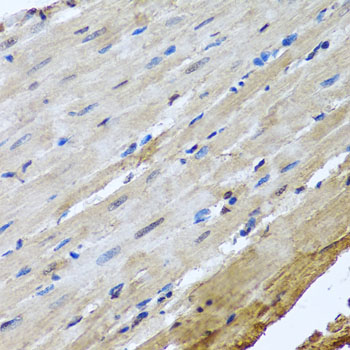

Immunohistochemistry of paraffin-embedded rat heart using NUMA1 at dilution of 1:100 (40x lens).